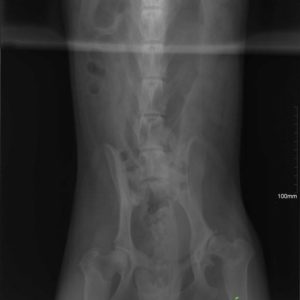

Köszönjük szépen Alexander Englert-nek, hogy Mex diszplázia műtéti költségét finanszírozta! Még 2 és fél hónap rehabilitáció és kereshetünk neki új gazdit! Category: HírekBy Csillag Alexandra2017-09-14 Share this post Share on FacebookShare on Facebook Share on XShare on X Author: Csillag Alexandra http://www.ebarvahaz.hu Post navigationPreviousPrevious post:SnowNextNext post:Közeleg a tél!Related postsPályázati eredmény2026-03-17Tami és a babák2026-01-22Cuki újoncaink2025-10-27IV. TÖKéletes nap az EbÁrvaházban2025-10-17Kutyás családi és nyílt nap a Kraft SE szervezésében2025-09-01Karamell kisgengszter berobbant a menhely életébe <32025-08-05